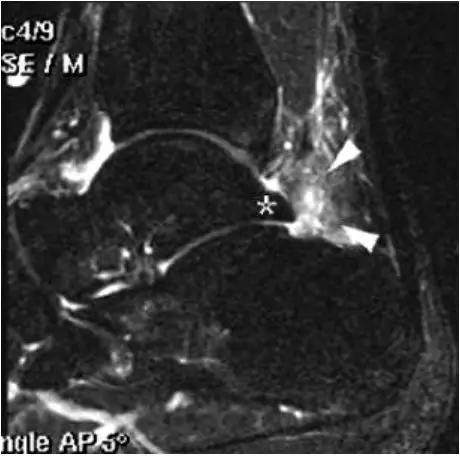

- MRI 检查示距后三角骨及周围软组织有水肿信号,距后三角骨和距骨之间正常的低信号纤维连接中断,出现液性信号。

3、MR表现:

- 三角籽骨或距骨后三角结构模糊和变形,T1WI信号降低, T2WI信号升高,

- 周围脂肪水肿,

- 踇趾长屈肌腱信号升高,见鞘膜积液,

- 胫骨后下跟骨上缘骨结构形态变化和信号异常,

- 三角籽骨和距骨退行性囊变。

三角籽骨综合征并跟腱滑囊积液